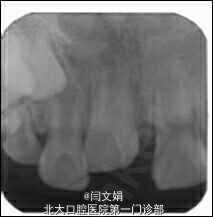

诊断:11挫入 治疗计划:11观察,定期复查牙髓活力 九个月后自行萌出,牙髓活力测同对照牙

年轻恒牙牙根未发育完成,外伤挫入后有自我萌出潜力,在临床上应密切观察